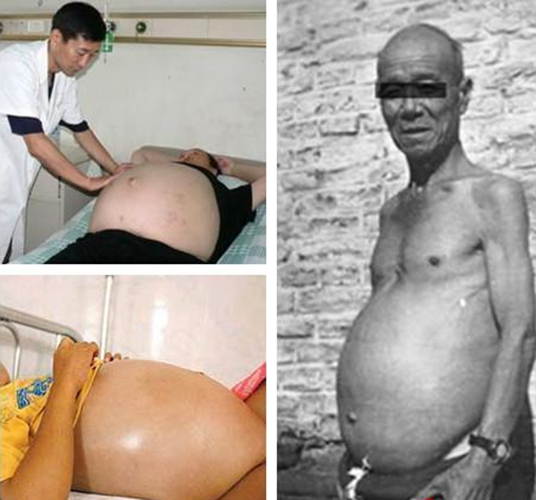

腹水圖片

有肚子腹水

有腹水患者

早期肝腹水肚子

早期肝腹水